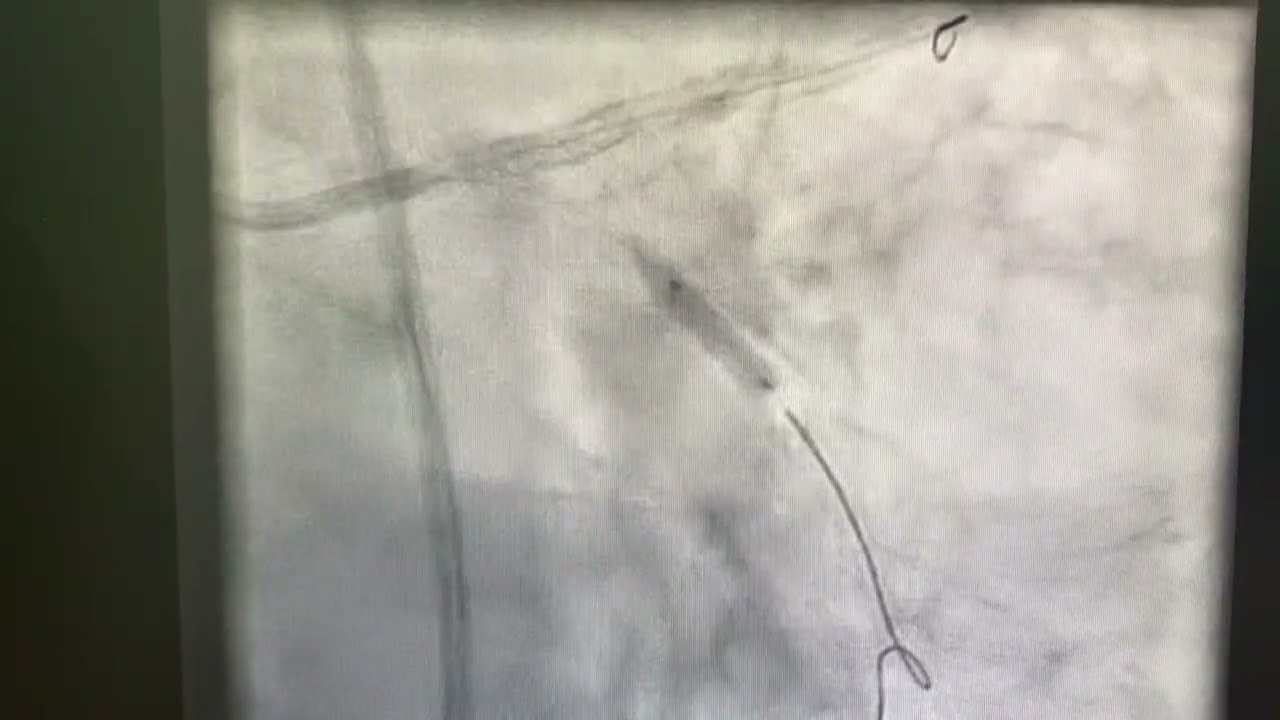

Left main coronary Intervention

Interventional cardiology

Mini Crush of left main artery Bifurcation with Rotablation of Ostial LCX